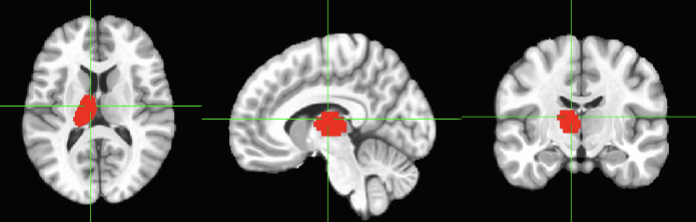

THALAMUS– This is the left hemisphere, we have a right

thalamus as well. The thalamus is also part of the

diencephalon, but it is much more. Remember that it is the

most important relay station for sensory information in the

brain. Almost all sensory information (visual and auditory

information, touch and taste) will have a synapse in the

thalamus before getting to other areas of the brain.